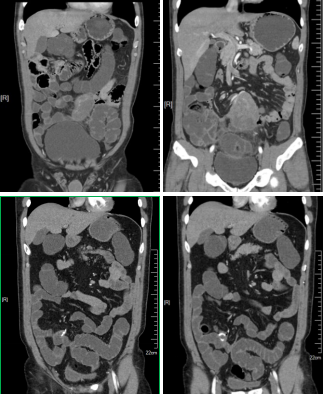

4、腹部應(yīng)用

病例一 女,71歲,反復(fù)發(fā)作心慌、 胸悶、 出汗,血糖2 . 56 mmol/ L。

動(dòng)脈期可見(jiàn)胰腺體尾部腫瘤明顯強(qiáng)化,CT-MIP圖可見(jiàn)供腫瘤血血管,VR圖像可清晰顯示腫瘤的供血血管以及與周圍組織的關(guān)系。 術(shù)后結(jié)果為胰腺體尾部胰島素瘤。

腹盆腔CT腸道充氣成像可見(jiàn)橫結(jié)腸脾曲結(jié)腸癌, 升結(jié)腸及降結(jié)腸多發(fā)息肉

腹腔鏡見(jiàn)腹腔粘連較重, 轉(zhuǎn)開(kāi)腹手術(shù), 取左側(cè)腹直肌切口, 逐層進(jìn)腹, 于橫結(jié)腸脾曲觸 及一腫塊, 遂行左半結(jié)腸切除術(shù)。

640層寬體探測(cè)器CT掃描速度快, 掃描時(shí)間只用了2 . 3 s,克服了胃腸道蠕動(dòng)造成的偽影 和漏層, 使腹部圖像質(zhì)量大大提高。 仿真內(nèi)窺鏡的圖像可觀察到黏膜的皺襞 , 不僅可清晰的 顯示小息肉及病變 , 而且可顯示出胃腸道造影及內(nèi)窺鏡易于遺漏的部位。